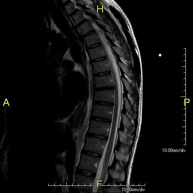

Prova diagnòstica no invasiva que consisteix en l'obtenció d'imatges d'alta definició anatòmica de la columna cervical mitjançant l'ús d'un camp electromagnètic i ones de ràdio (com un emissor i un receptor). No utilitza radiació ionitzant. Indicacions: traumatisme, degeneració de la columna, hèrnies. - RM de columna dorsal

Prova diagnòstica no invasiva que consisteix en l'obtenció d'imatges d'alta definició anatòmica de la columna dorsal mitjançant l'ús d'un camp electromagnètic i ones de ràdio (com un emissor i un receptor). No utilitza radiació ionitzant. Indicacions: traumatisme, problemes degeneratius, hèrnies, tumors. - RM de Columna lumbar

Prova diagnòstica no invasiva que consisteix en l'obtenció d'imatges d'alta definició anatòmica de la columna lumbar i sacre mitjançant l'ús d'un camp electromagnètic i ones de ràdio (amb un emissor i un receptor). No utilitza radiació ionitzant. Indicacions: traumatismes, ciàtica, hèrnies discals, tumors, infeccions - RM Mielografia

Prova diagnòstica no invasiva que consisteix en l'obtenció d'imatges d'alta definició anatòmica de la medul·la espinal i les arrels nervioses mitjançant l'ús d'un camp electromagnètic i ones de ràdio (amb un emissor i un receptor), així com seqüències d'estudi especials (mielogràfiques). No utilitza radiació ionitzant. Indicacions: hèrnies, compressions medul·lars. - RM de Plexe braquial

Prueba diagnóstica no invasiva que consiste en la obtención de imágenes de alta definición anatómica de la columna cervical mediante el empleo de un campo electromagnético y ondas de radio (con un emisor y un receptor). No utiliza radiación ionizante. Indicaciones: traumatismo, degeneración de la columna, hernias. - RM Columna Dorsal

Prueba diagnóstica no invasiva que consiste en la obtención de imágenes de alta definición anatómica de la columna dorsal mediante el empleo de un campo electromagnético y ondas de radio (con un emisor y un receptor). No utiliza radiación ionizante. Indicaciones: traumatismo, problemas degenerativos, hernias, tumores. - RM Columna Lumbar

Prueba diagnóstica no invasiva que consiste en la obtención de imágenes de alta definición anatómica de la lumbar y sacra mediante el empleo de un campo electromagnético y ondas de radio (con un emisor y un receptor). No utiliza radiación ionizante. Indicaciones: traumatismos, ciática, hernias discales, tumores, infecciones. - RM Sacro-cóccix